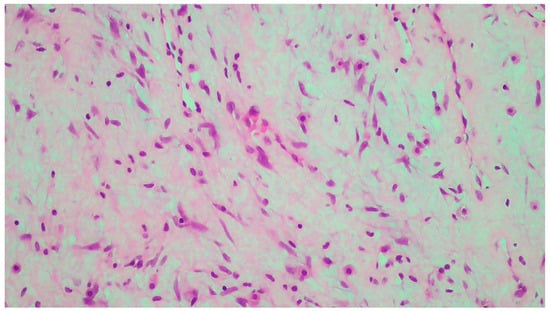

2. Case Report